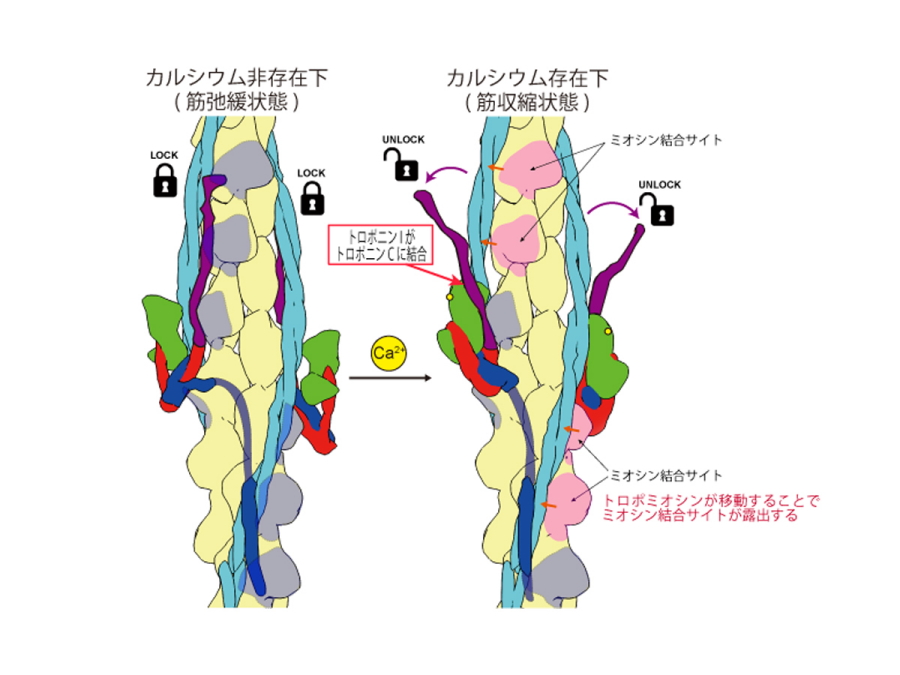

臨床心臓構造学―不整脈診療に役立つ心臓解剖 | 修,井川 |本。テキスト臨床心臓構造学: 循環器診療に役立つ心臓解剖 | 井川修。テキスト臨床心臓構造学: 循環器診療に役立つ心臓解剖 | 井川修。新米 コシヒカリ 30キロ 千葉県産。かわぐち心臓呼吸器病院新築工事、同改修工事|医療・福祉。AlphaFold 3 の超完全な解体、上海交通大学の Zhong Bozitao 氏。\r自炊用に裁断したバラバラ状態のため普通には読めません。総説:αシヌクレイン凝集体の立体構造とプリオン様性質 | コスモ。#裁断済み#自炊用#医学書。卧式加工中心SPACE CENTER MA-600HⅢ | 产品导航| 大隈株式会社。心臓の鼓動を制御する分子メカニズムをついに可視化 | 大阪大学。新品購入したものを裁断しています。臨床工学技士のための「臓器不全」をまなぶ | 臨床工学技士の。計算生命科学の基礎9 タンパク質の立体構造予測-AlphaFold以前。\r裁断した状態のため「全体的に状態が悪い」にしています。\rご理解のある方のみご購入をお願いします。ziostation2を用いて心臓MRI検査の総合的な画像解析を可能に